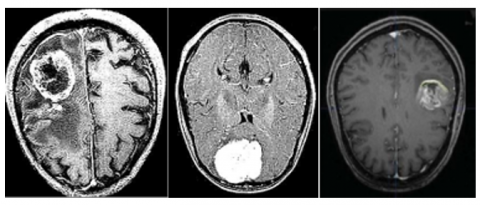

The research dataset originated from Kaggle while containing 3,000 images. Three thousand images in the dataset receive total equal distribution between "Yes" with 1,500 images and "No" also having 1,500 images thereby creating a balanced dataset which can be seen in Figures 8 and 9. A perfectly balanced dataset offers several advantages because it reduces model biases while providing equal representation of the classes which leads to better classification outcomes.

Image resolution and acquisition conditions: The horizontal and vertical resolution of each dataset image equals 96 dots per inch. Image collection takes place through standardized acquisition procedures that create uniformity for minimized brightness and contrast differences as well as noise levels. Standardized acquisition conditions along with these conditions lead to optimized segmentation performance through uniform image quality and format.

Preprocessing requirements: The images receive basic processing steps including dimension standardization through cropping and resizing before they can be employed for educational functions. Pixel intensity values within the dataset benefit from technical preprocessing through intensity normalization as an approach to create consistent values. Model generalization together with pattern detection effectiveness improves with this essential step.

Data distribution that evenly distributes images across the dataset decreases the time needed to manage data especially in situations where classes do not match. An unbalanced dataset causes model predictions to become biased because it enables the model to recognize one class more frequently than the other such as "No Tumor" compared to "Tumor." This dataset maintains a balanced structure which delivers trustworthy and impartial training results to deep learning-based segmentation operations.

Figure 8. Brain MRI images that have tumor